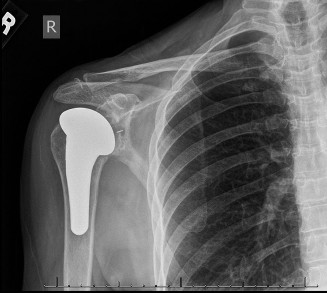

Humeral head defects >40% (Answers D, E) frequently require a large allograft or prosthetic reconstruction. If a prosthetic option is chosen, some authors recommend placing the prosthetic glenoid component in 10 to 15 degrees of retroversion for an anterior dislocation and doing the opposite for a posterior dislocation. Objectives: Did you learn...? To recognize the common presentation of a patient with a chronic dislocation? To recognize the pathoanatomic changes associated with a chronic dislocation? The various treatment options and indications for their use? CASE 17 Dr. Anna Cohen-Rosenblum A 61-year-old, right-hand-dominant female presents with 5 years of gradually worsening right shoulder pain. The pain is worse at night and she is finding it gradually more difficult to perform certain activities such as combing her hair, putting on a coat, and reaching for objects on high shelves. Past medical history includes hypertension and hyperlipidemia, both well controlled with medication. Physical examination reveals that the right shoulder appears flatter in contour compared with the contralateral side. She has diffuse tenderness to palpation about the right shoulder glenohumeral joint; range of motion of the shoulder decreased in external rotation; and 5/5 strength in the rotator cuff muscles. Imaging is shown in

Figures 2–48 and 2–49.

Figure 2–48

Figure 2–49

Based on the information and imaging, what is the most likely diagnosis?

The correct answer is (B). The patient’s chronic pain, difficulty with external rotation, flattened appearance, combined with the imaging showing narrowed joint space, subchondral sclerosis, and osteophytes at the inferior aspect of the humeral head lead to the diagnosis of glenohumeral osteoarthritis. In addition, the patient has no signs of cuff deficit on examination and no history of trauma, so Answer A is incorrect. Cuff tear arthropathy (Answer C) would also be less likely given her lack of weakness combined with imaging showing typical signs of osteoarthritis without a high-riding humeral head as would be characteristic of a massive cuff tear with resulting arthropathy. Finally, Answer D is incorrect because, even though it is probable a person her age would have a labral tear, it would manifest more as mechanical symptoms and/or instability.

The patient undergoes a total shoulder arthroplasty via deltopectoral approach. At her 2-week postoperative visit, the incision is healing well and her pain is controlled with 1 to 2 tablets of hydrocodone-acetaminophen daily. You give her a prescription for physical therapy. Four weeks later, the patient returns to clinic complaining of an increase in shoulder pain as well as weakness for the past 3 days, especially when getting dressed. She does not recall any traumatic event. On examination her incision remains clean, dry, and intact; there is a positive finding of weakness when resistance is applied to the arm in an adducted and internally rotated position behind the back. X-rays are shown in Figure 2–51.

Figure 2–51

The correct answer is (C). During the deltopectoral approach, the subscapularis tendon is detached from the anterior humerus so the humeral head may be exposed. The tendon is reattached after placement of the components, and there is a postoperative risk of repair failure, especially during rehabilitation. Precautions to avoid in rehabilitation include limiting external rotation of the shoulder and avoiding such movements as pushing out of a chair. Pendulum exercises and passive range of motion supervised by physical therapy are advised, and active range of motion of the elbow, wrist, and hand should be encouraged to avoid stiffness. Choice “A” is incorrect because the patient’s symptoms are more consistent with subscapularis tear, and there is no radiographic evidence of loosening. Choice “B” is incorrect because infection is more associated with loosening. Choice “D” is incorrect because axillary nerve palsy would likely present as weakness with shoulder abduction and/or sensory changes in the skin around the deltoid. Objectives: Did you learn...? Recognize the clinical presentation of glenohumeral osteoarthritis? Treat a patient with glenohumeral osteoarthritis?